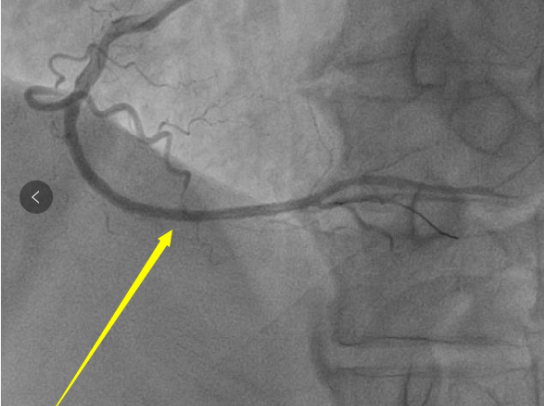

随后 , 心血管中心为詹先生做了冠脉造影 , 造影显示 , 右冠状动脉中段以远完全闭塞 , 前段支也有狭窄 。

时间就是生命 , 肖主任带领团队立即为詹先生开通右冠急性闭塞病变 , 进行血运重建 , 并安装血管支架 。 最终手术圆满完成 , 闭塞的右冠状动脉恢复血流 , 患者胸痛症状缓解 , 生命体征正常 。